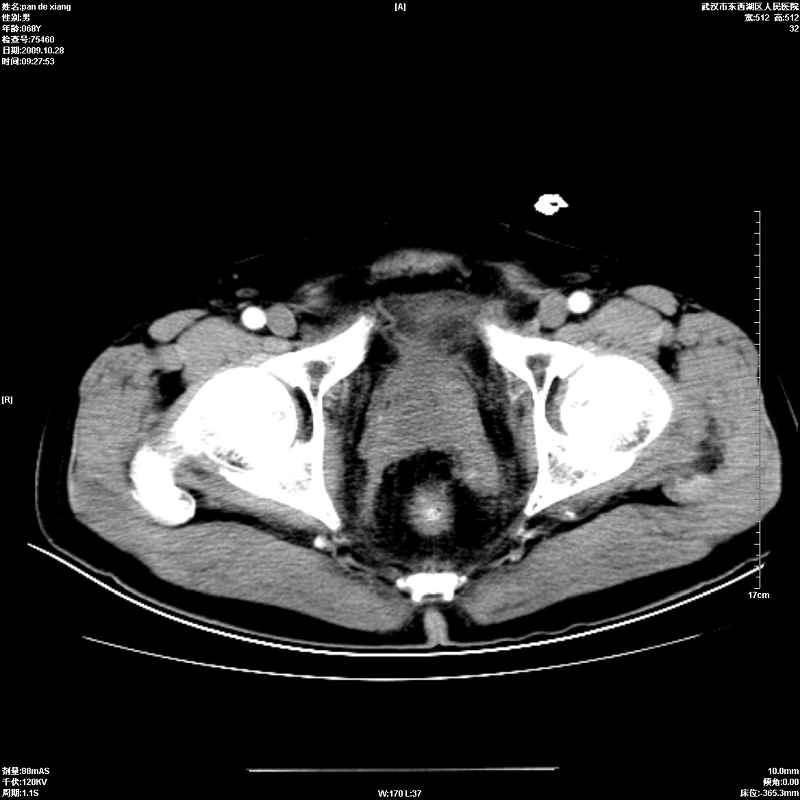

以下是引用杀毒软件在2009-10-28 20:41:00的发言:[br]结合临床考虑---白血病双肾改变或淋巴瘤。

以下是引用zxl51642在2009-10-29 9:59:00的发言:[br]结合临床“单克隆免疫球蛋白血症”,考虑双肾为继发损害并肾功能不全(尿中大量igg及少量iga、igm等大分子免疫球蛋白滤出所致继发损害),椎前软组织肿块为髓外造血。与浆细胞瘤有区别,平扫时有战友说的很清楚。